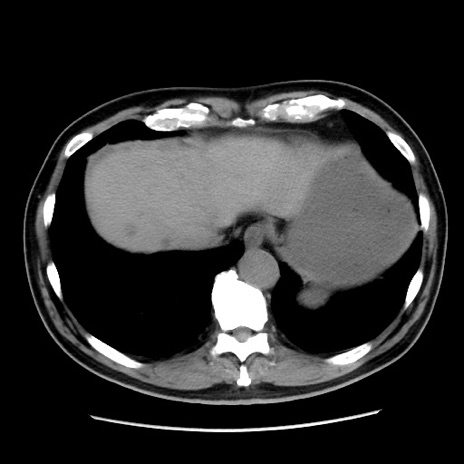

症例16(横断像)

【症例】 70歳代男性

【主訴】 腹痛、嘔吐

【現病歴】 約1ヶ月前より間欠的に腹痛と嘔吐あり、当院消化器内科を受診したところCTで多発する肝臓のLDAを指摘され、精査中であった。以降は消化器症状は安定していたが、2日前より嘔気と腹痛があり、同日より排便・排ガスが消失した。改善認めず、 本日、救急外来を受診した。

【既往歴】 大腸ポリープ切除後。

【身体所見】意識清明・会話良好、BT 36.3℃、BP 127/80mmHg、 P 80bpm、腹部:膨満あり、平坦・軟、上腹部正中および下腹部正中に圧痛あり、反跳痛なし、筋性防御なし。

【データ】WBC 7200、CRP 0.77